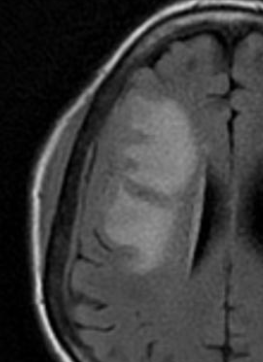

Ménigiome En plaque

- Extension durale diffuse

- Extension extra-cranienne ++ (orbite, tissus mous, calvaria)

- Bénin mais Souvent difficile à résquer